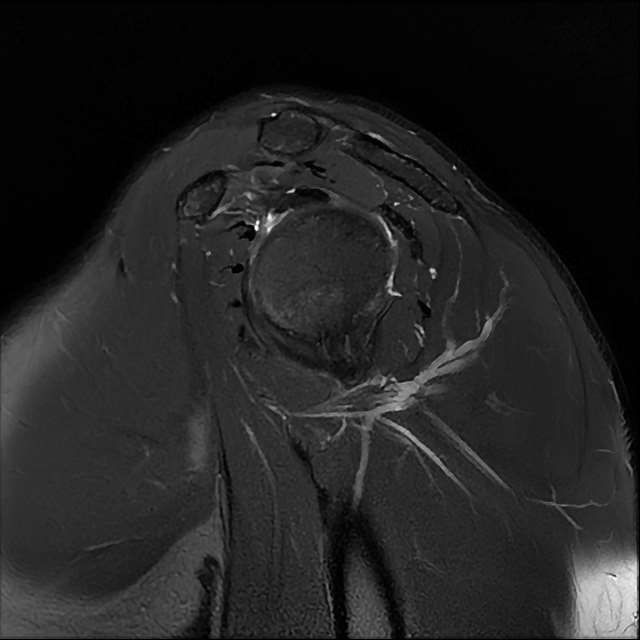

오른쪽 어깨 와순파열 및 점액낭염이 보인다고 하는데 상태를 알고 싶습니다

MRI 사진상 와순파열 점액낭염 등이 있다고 하는데..심한 상태인가요?

MRI상 와순파열, 회전근개 부분파열 등이 있으며 일부 염증소견이 있습니다.